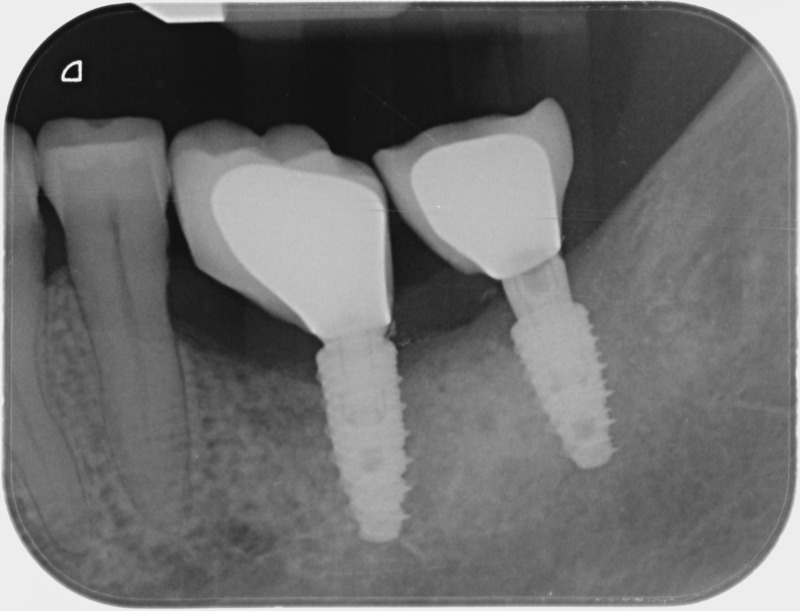

• Couronnes sur implants : Lorsqu’un implant est posé en remplacement des racines d’une dent, il est conçu pour recevoir d’abord un pilier vissé puis une couronne céramique. Le couple couronne - implant se substitue à la dent manquante pour en assurer les mêmes fonctions. Nous pouvons également adapter un bridge sur plusieurs implants dans le cas d’un édentement plus important.

Avant